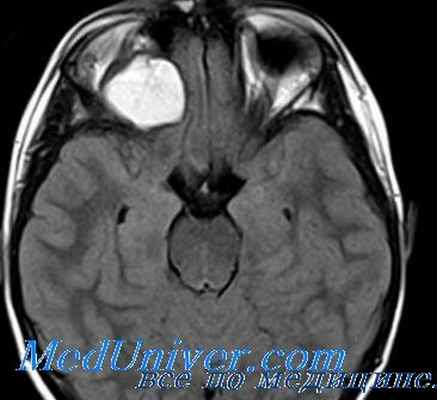

Репозиция глаза всегда резко затруднена. На глазном дне одинаково часто наблюдают застойный диск или атрофию зрительного нерва. При росте опухоли близи склерального кольца отек диска зрительного нерва выражен особенно сильно, вены резко расширены, извиты, с синюшным оттенком. Наблюдающиеся кровоизлияния вблизи диска возникают за счет непроходимости центральной вены сетчатки. В отличие от менингиомы, глиома никогда не прорастает твердую мозговую оболочку, но по стволу зрительного нерва может распространяться в полость черепа, достигая хиазмы и распространяться на контралатеральный зрительный нерв. Интракраниальное распространение сопровождается нарушением функций гипоталамуса, питуитарной железы, повышением внутричерепного давления. Диагноз глиомы ставят на основании данных компьютерной томографии, с помощью которой можно не только визуально наблюдать увеличенный зрительный нерв в орбите, но и судить о его распространении по каналу зрительного нерва в полость черепа. Ультразвуковое сканирование недостаточно информативно, так как представляет изображение только проксимальной и средней трети зрительного нерва. МРТ более информативно при интракраниальном распространении опухоли.

Контрастная МРТ при глиомк зрительного нерва